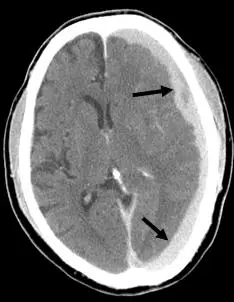

頭部外傷的病人, CT 影像如下圖,箭號所指的是: 圖片

本張為頭部 CT 無對比劑橫切面(non-contrast CT, NCCT)。兩個箭號分別指向雙側大腦半球顱骨內板下方的新月形(crescent-shaped)高密度病灶:

• 形態:病灶呈新月形,沿腦表面分布,內緣凹向腦實質,符合硬腦膜下腔積血的形態。並非雙凸(biconvex/lentiform)形,可排除硬腦膜上血腫(EDH)。

• 密度:病灶呈高密度(hyperdense,接近白色),代表急性出血(新鮮血液中血紅素密度約 60–80 HU)。

• 分布:病灶跨越顱縫(不受顱縫限制),沿顱骨內板走行;SDH 因出血在硬腦膜與蜘蛛膜之間的硬腦膜下腔,可自由跨越顱縫,與 EDH(受顱縫限制)形成對比。

• 雙側性:兩側均可見病灶,約 20% 的硬腦膜下血腫為雙側性,雙側對稱時可能無明顯中線偏移,增加診斷難度。

綜合以上特徵,影像表現最符合**雙側急性硬腦膜下血腫(